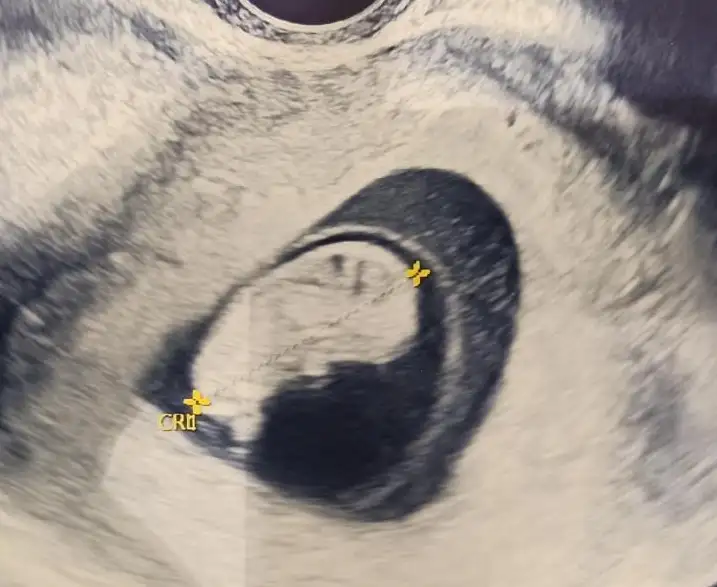

Ben bennn , lütfeennnn bana da bakınnn 9+3 tu burda

Eklentiler

• bebiş.webp

20,5 KB · Görüntüleme: 75